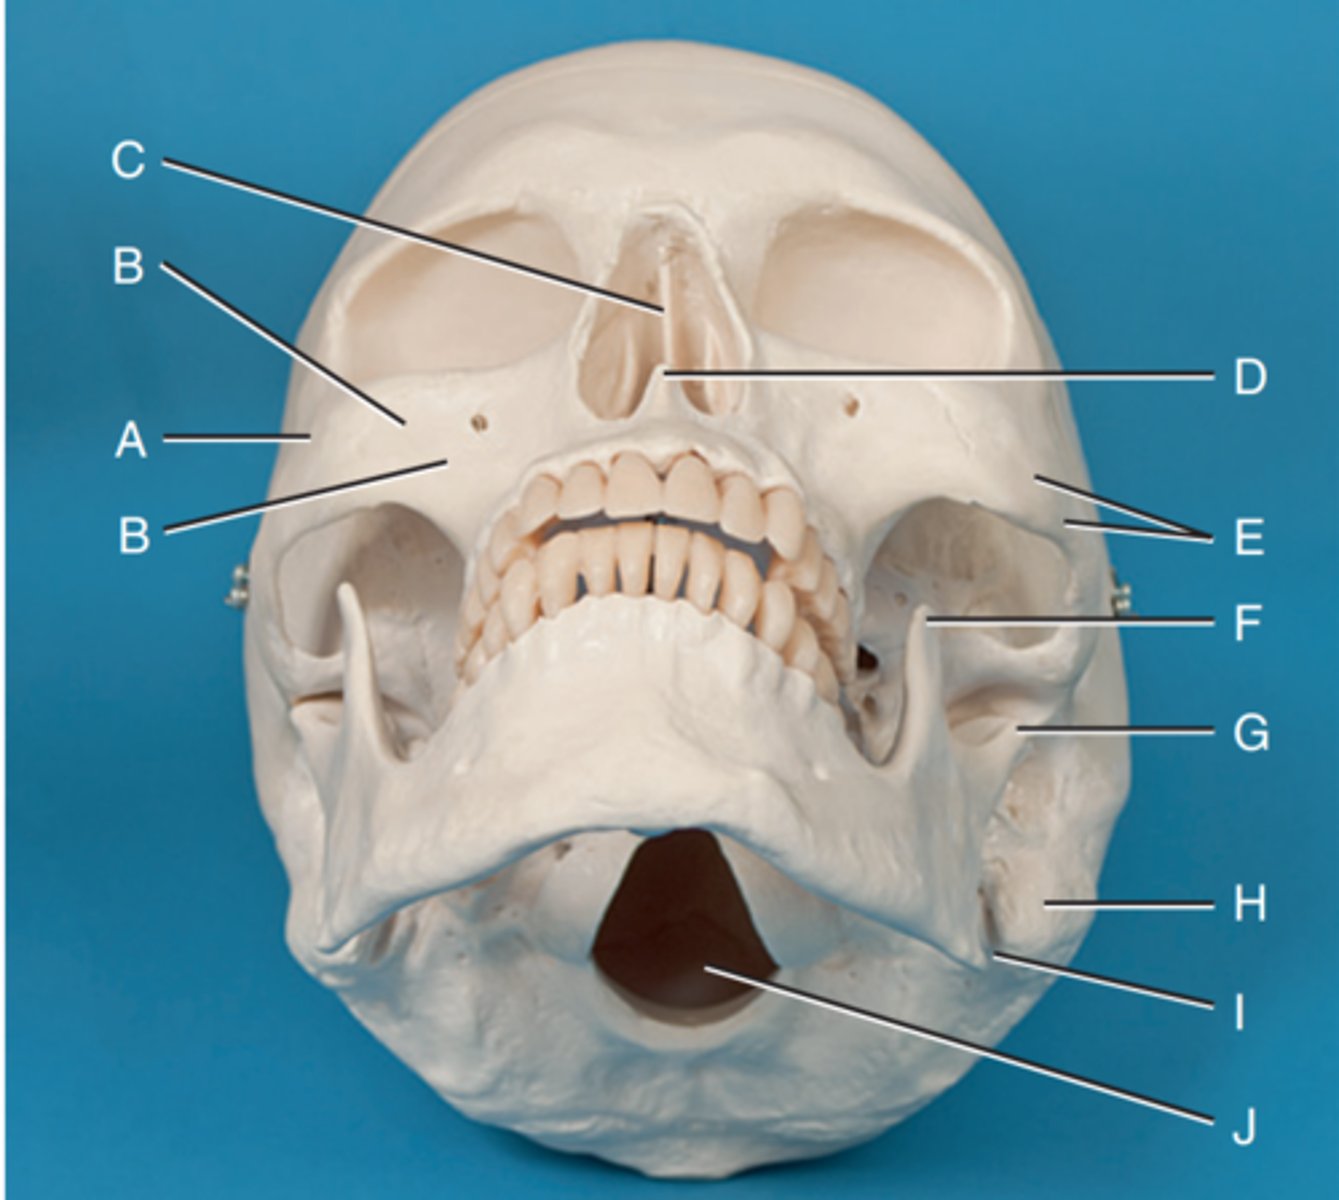

Zygomatic prominence

Label A

Body of maxilla

Label B

Bony nasal septum

Label C

Anterior nasal spine

Label D

Zygomatic arch

Label E

Coronoid process

Label F

Condyle

Label G

Mastoid process of temporal bone

Label H

Angle of mandible

Label I

Foramen magnum

Label J